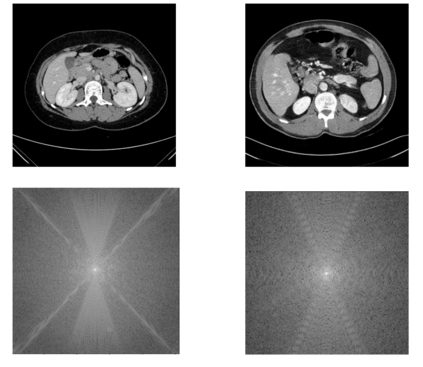

In many clinical settings, the use of both Computed Tomography (CT) and Magnetic Resonance (MRI) is necessary to pursue a thorough understanding of the patient's anatomy and to plan a suitable therapeutical strategy; this is often the case in MRI-based radiotherapy, where CT is always necessary to prepare the dose delivery, as it provides the essential information about the radiation absorption properties of the tissues. Sometimes, MRI is preferred to contour the target volumes. However, this approach is often not the most efficient, as it is more expensive, time-consuming and, most importantly, stressful for the patients. To overcome this issue, in this work, we analyse the capabilities of different configurations of Deep Learning models to generate synthetic CT scans from MRI, leveraging the power of Generative Adversarial Networks (GANs) and, in particular, the CycleGAN architecture, capable of working in an unsupervised manner and without paired images, which were not available. Several CycleGAN models were trained unsupervised to generate CT scans from different MRI modalities with and without contrast agents. To overcome the problem of not having a ground truth, distribution-based metrics were used to assess the model's performance quantitatively, together with a qualitative evaluation where physicians were asked to differentiate between real and synthetic images to understand how realistic the generated images were. The results show how, depending on the input modalities, the models can have very different performances; however, models with the best quantitative results, according to the distribution-based metrics used, can generate very difficult images to distinguish from the real ones, even for physicians, demonstrating the approach's potential.